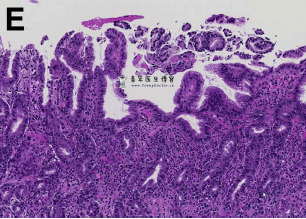

内镜下活检后,组织病理学提示粘膜和粘膜下层中性粒细胞广泛浸润(图E,F)。

如果活检取到了足够的粘膜下层,则通过活检即可确认诊断蜂窝织炎性胃炎。